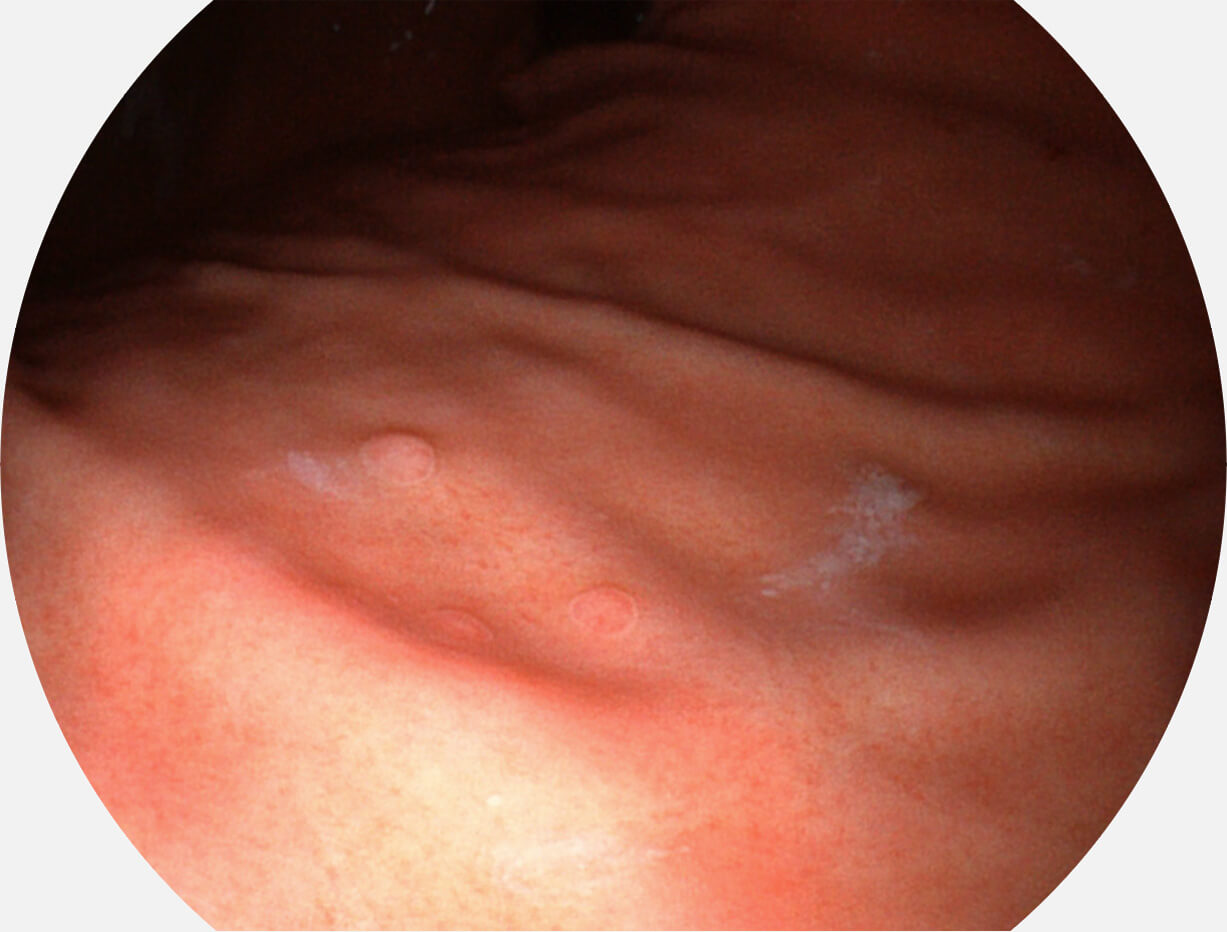

白光图像

VIST图像

Versatile Intelligent Staining Technology, VIST

强调浅层黏膜结构的同时,保证照明亮度和提升浅层微血管与中层血管颜色对比度,病变边界更清晰。